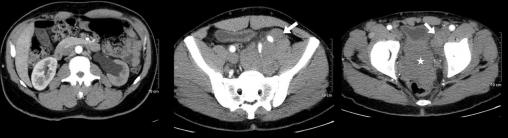

Patient de 51 ans admis en urgence pour œdème du membre inférieur gauche et hydronéphrose gauche, révélateurs d’un cancer de la prostate localement avancé (stade IV). Un bilan d’extension est réalisé par une tomodensitométrie avec injection. Volumineuse masse prostatique (★) associée à des adénopathies iliaques gauche compressives (flèches).